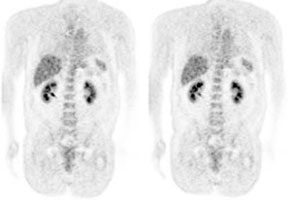

3- Renal/Urinary bladder- Unlike glucose, FDG is filtered by the glomerulus and not resorbed [54]. Hydration and frequent voiding promote diuresis and help to decrease the radiation dose to the genitourinary tract [4]. The use of IV hydration and IV lasix (0.5 mg/kg up to 40 mg with 3 successive urinary bladder voidings) can help to decrease/clear ureteral and urinary bladder activity in cases in where there are equivocal pelvic findings [153].

|

Genitourinary activity: The image below demonstrates normal renal and hepatic activity. |

|

|

|

Genitourinary activity: The image below demonstrates activity within the collecting system of a transplanted kidney (black arrows). This should not be mistaken for an abnormality. |

|

|

|

Bladder cancer: Dilute urinary activity in this patient's bladder allowed accurate detection of their bladder cancer (white arrows on CT, black arrows on PET scan). In general, urinary excretion of FDG limits evaluation of urinary tract malignancies, however, hydration and diuresis can improve diagnostic accuracy. |

|

|